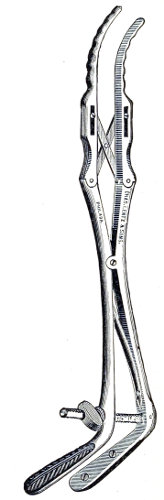

Fig. 4.—Double tenaculum.

The examination of the uterus and other pelvic structures is often facilitated by dragging the uterus downward with a tenaculum while the vaginal or the bimanual examination is being made. Sensation in the cervix is so slight that little or no pain is experienced in this procedure. The anterior or posterior lip of the cervix is caught with the single or the double tenaculum (Fig. 4), guided along the vaginal finger or introduced through the speculum, and the uterus is drawn down by an assistant in case the bimanual examination is being made, or by the external hand of the examiner in case a simple vaginal examination is made. When this is done the utero-sacral ligaments are made tense, and can be felt like two cords extending from the sides of the cervix outward and backward to the pelvic wall. The posterior surface of the uterus can be palpated often as high up as the fundus. The method is especially useful when the examination is made by the rectum, and in this way the whole posterior surface and the fundus of the uterus may be palpated (Fig. 5).